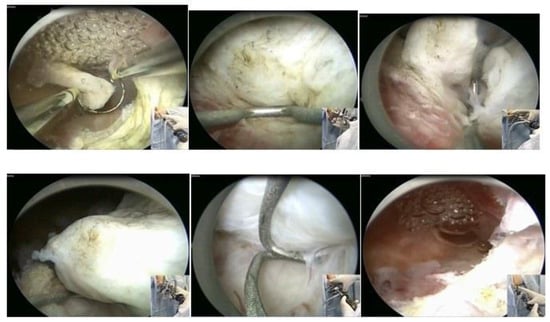

In our service, the most performed technique is using the 5 Fr tweezers or scissors. Initially, the endometrium is incised around the nodule until accessing the plane of the pseudocapsule; then, with the forceps or the body of the hysteroscope, entering between the nodule and the myometrium, the release is initially performed, laterally first and then centrally, until its complete release (Figure 7).

At the end, the nodule will be loose in the cavity and can be fragmented or completely removed with grasping forceps. In cases of difficulty in removing the nodule from the cavity, the patient should be instructed to return in 7 to 10 days, during which time either the nodule will be spontaneously expelled by the patient—she should be oriented about this possibility—or it will have drastically decreased in size, allowing its removal.

When using instruments with energy, we can use the bipolar Collins loop of a miniresectosope system [26] (Figure 8) or the LASER fiber to incise the endometrium around the myoma. However, all mobilization is performed mechanically with forceps, a loop, or the resectoscope itself.

Figure 7. Office hystreroscopic myomectomy with scissor.

Figure 8. Office hysteroscopic myomectomy with miniresectoscope.